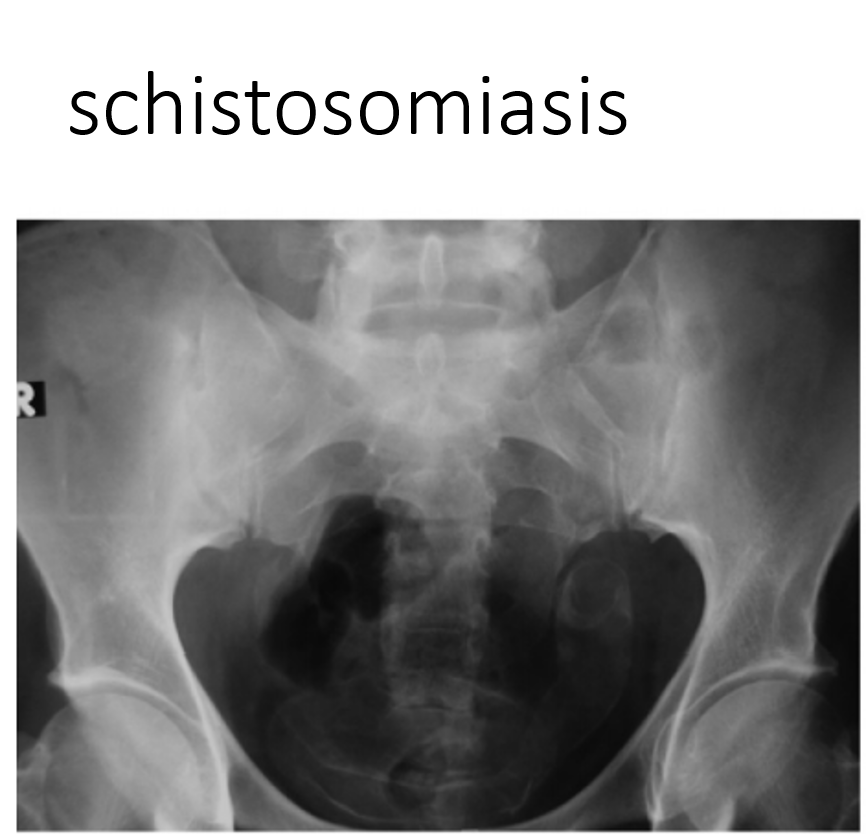

schistosomiasis